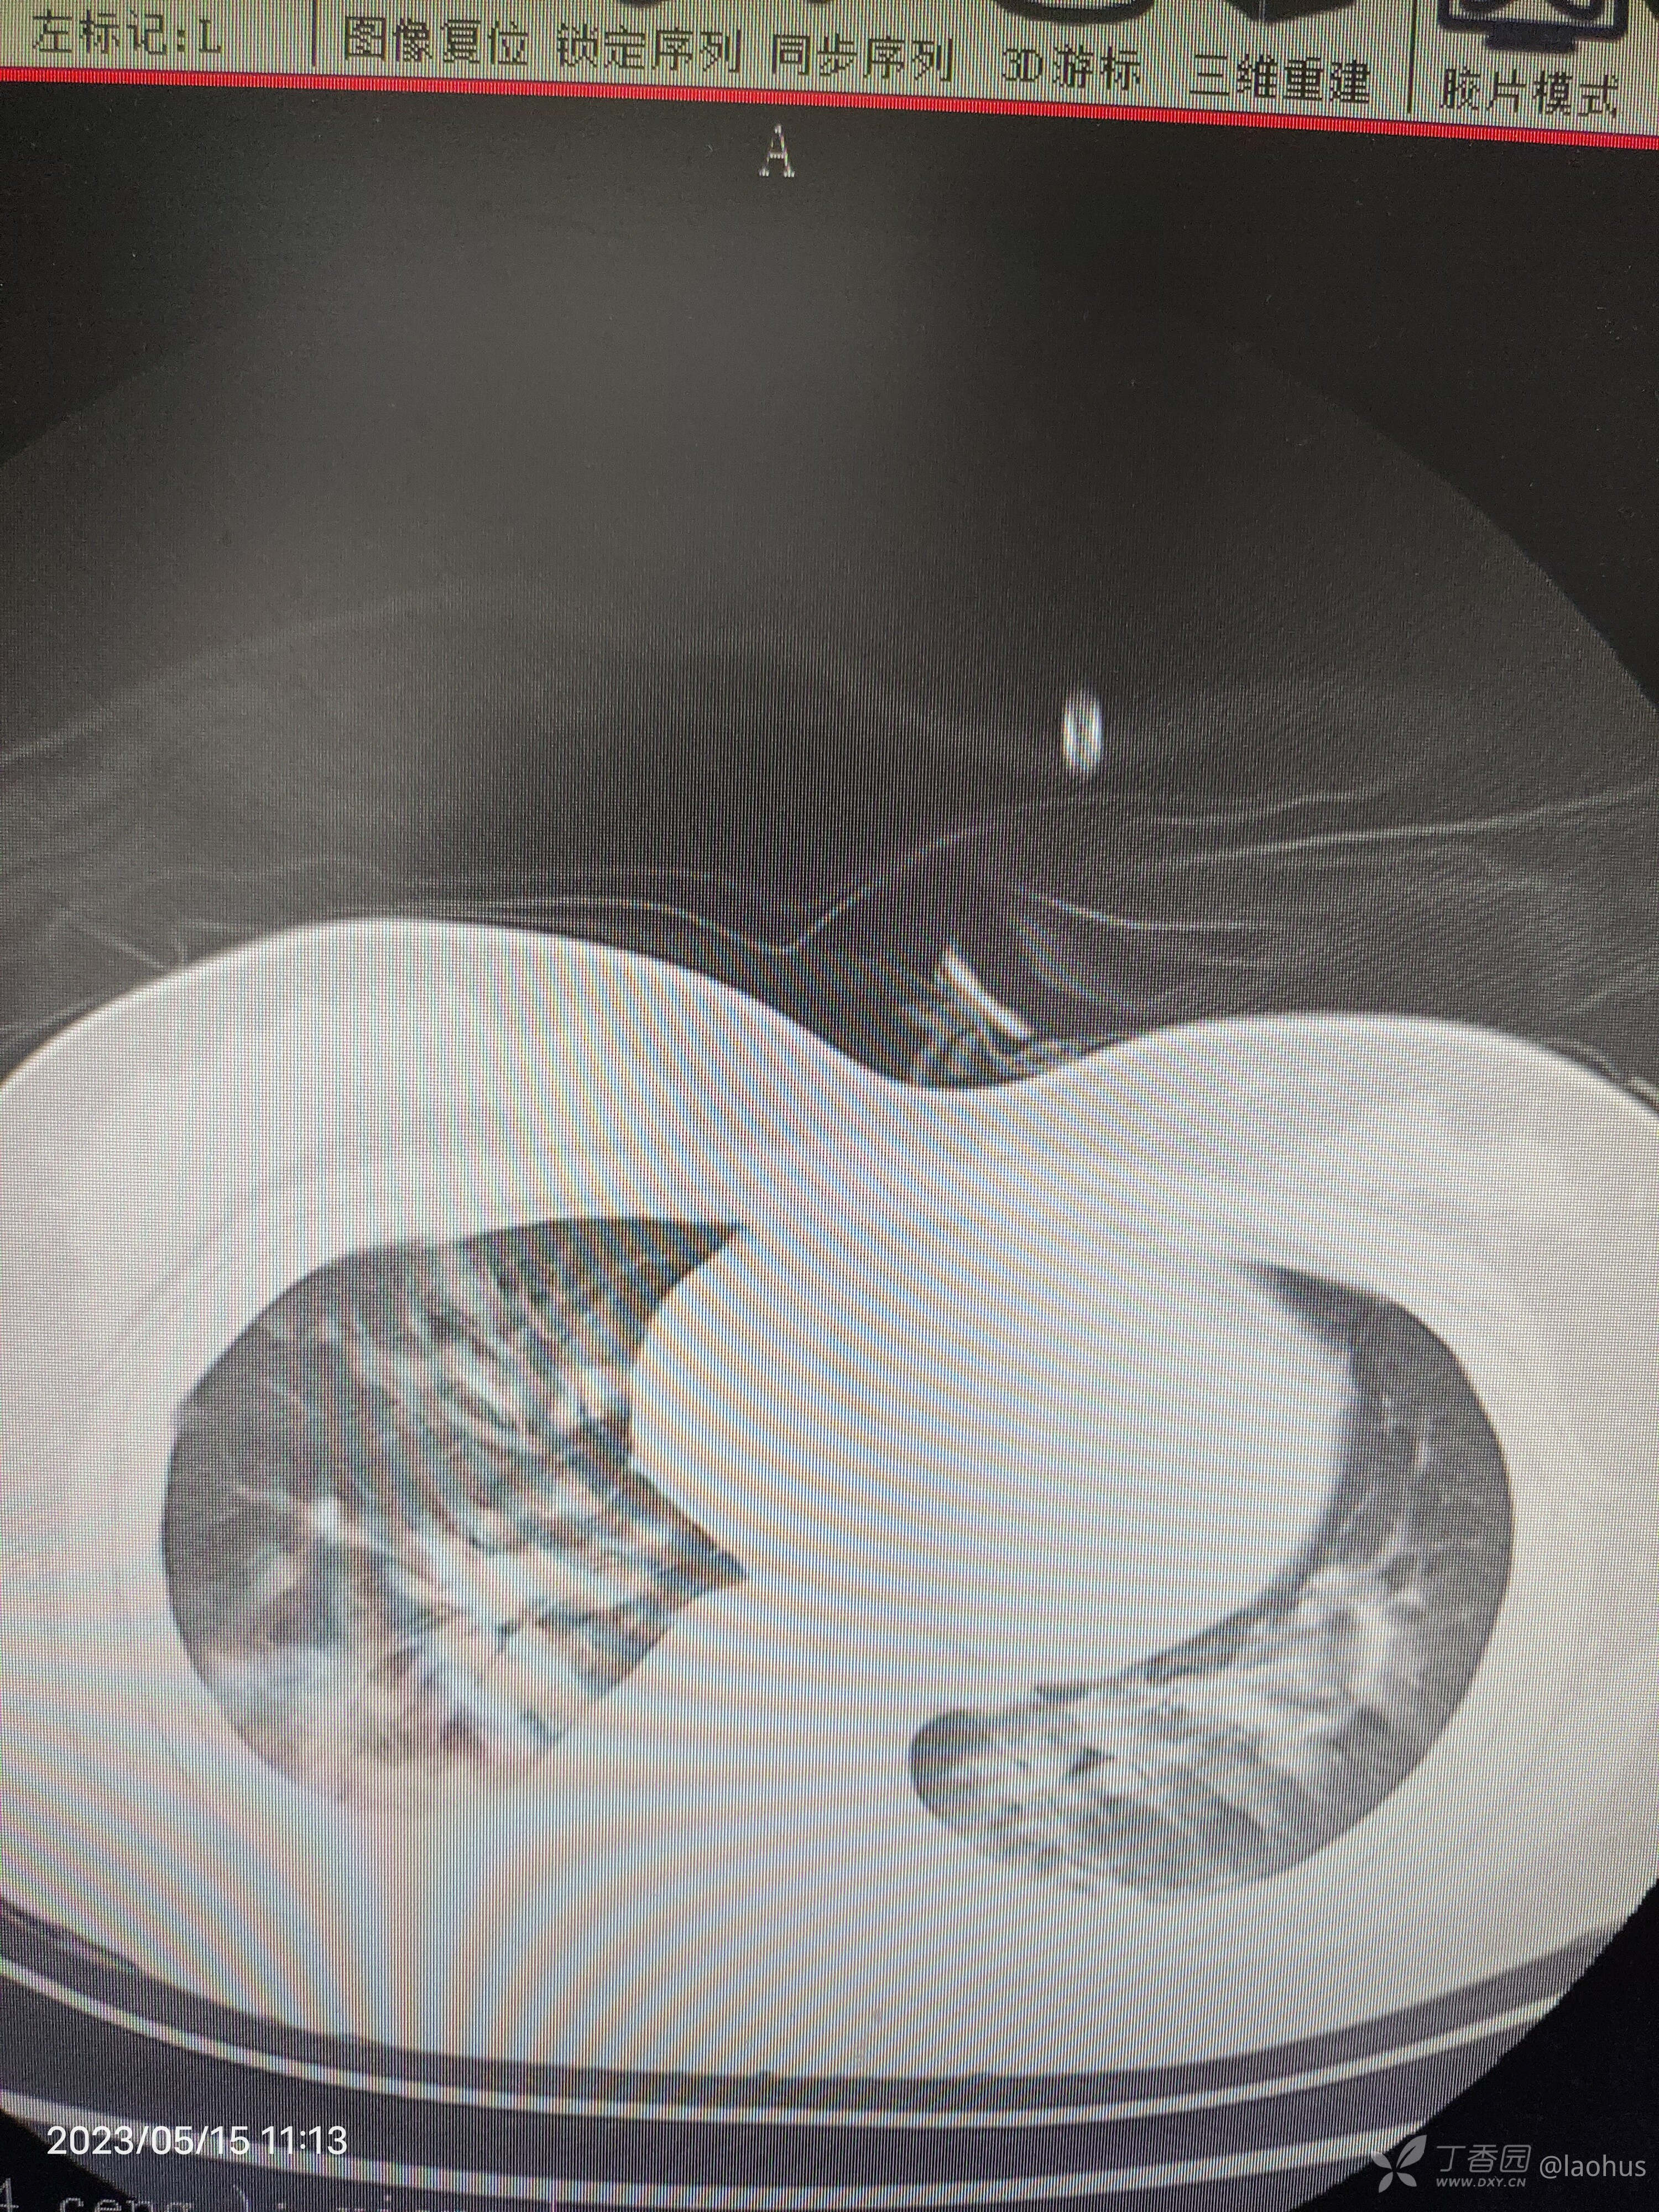

第二天CT